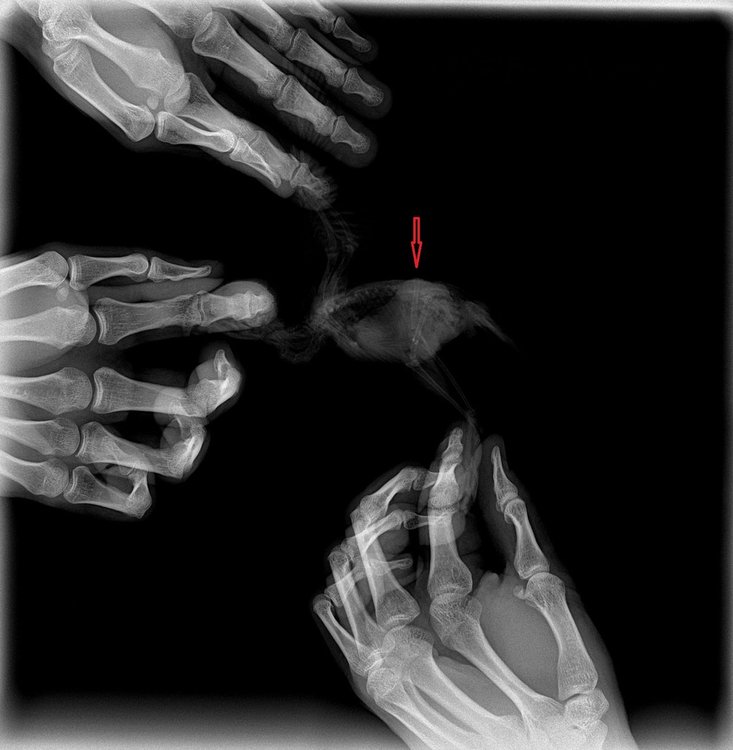

В общем в ветеринарке при нас принесли птенца какарика на услыпление, в ходе разговора выяснили что проблема в лапке. Нам стало его жалко и решили взять себе. Думали вывих. В итоге с горем пополоам записались на прием к орнитологу по совместительству, и на рентгене уже поняли, что у птенца закрытый перелом правой шейки бедра (фото прилагаю). Из информации которая есть - птенцу 28 дней, травма была получена, как нам сказали 8 дней назад. Прошлые хозяева никак не лечили, насколько я понял. Аппетит у птенца хороший, кормим немолочной 5 злаковой кашей хайнц, пробуем давать вареную морковь. Ведет себя бодро. кал нормальный (не жидкий и не твердый) зеленого цвета. В районе травмы опухлость, кожа равномерно бордового цвета (сфоткать возможности сейчас нету, но там никаких отличающихся очагов чего либо или отличий по цвету нету), кожа тепленькая, синюшности и холода нету. Нерв, судя по всему не сильно пострадал, потому что пальчики сжимает, но слабо. Самой лапкой пошевеливает, насколько это получается возможным. Врач нам дал Мелоксидил 1.5 мг и Байтрил 2.5%, дополнительно сами с кашей даем кальция глюконат (посоветовали). Собственно вопрос - на что нам можно надеяться в данной ситуации? Есть шанс, что лапка как нибудь заживет и птица, пусть хромая, но сможет жить, или она все время будет испытывать сильную боль? Операцию по костям (резекция вроде) как в нашем случае у нас в городе (Ижевск) не делают - нет квалифицированных специалистов. Поковырять могут, но результат не гарантируют и все с большими оговорками и кучей "если". Очень надеюсь на ваш ответ, потому что мы в тупике и помощи от местных ветеринаров широкопрофильников получить не можем.

6t-k-_aRLps.jpg

REeKV36qOQE.jpg

z5l-BG2-HEs.jpg

Попробовали сделать фото кожи в месте травмы. Если очень надо, можем переделать. Из того что заметил сегодня - со стороны больной лапки снизу тоже какой то выступ, которого со стороны здоровой лапки нету. Птенца держим в коробке с опилом и больная лапка все время в таком положении. Первый день пробовали навязать какое то подобие бандажа, зафиксировать бедро, но как сказал врач и как сам уже почитал, смысла в нем в данной ситуации нет. Или есть?

купили травма-гель, намазали. в районе бедра гематома темного цвета и бедренная кость упирается в кожу.